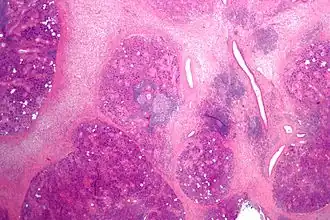

![]() Micrografía de una sialadenitis crónica | ||

La sialoadenitis es un término médico que significa inflamación de una de las glándulas salivales, que puede ser un evento agudo (temporal) o crónico y recurrente.